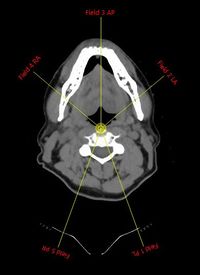

5-felt teknikken.

Som standard 5 felter (Se figuren).

Feltretninger:

• Udgangspunktet er 50°, 160°, 200°, 310° og 0°, men tilret felterne efter patientens anatomi.